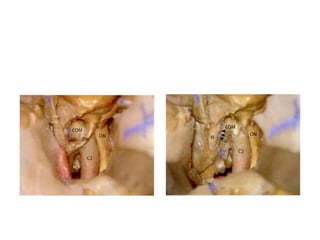

Laceral carotid lies over the Foramen lacerum not passing through

Foramen lacerum - Foramen lacerum floor is occupied by FCB [

Fibrocartilagenous basalis ] -- Note Fibrocartilagenous basalis at

laceral segment in both photos

Laceral carotid liesover the Foramen lacerum not passing through Foramen lacerum - Foramen lacerum floor is occupied by FCB [ Fibrocartilagenous basalis ] -- Note Fibrocartilagenous basalis at laceral segment in both photos